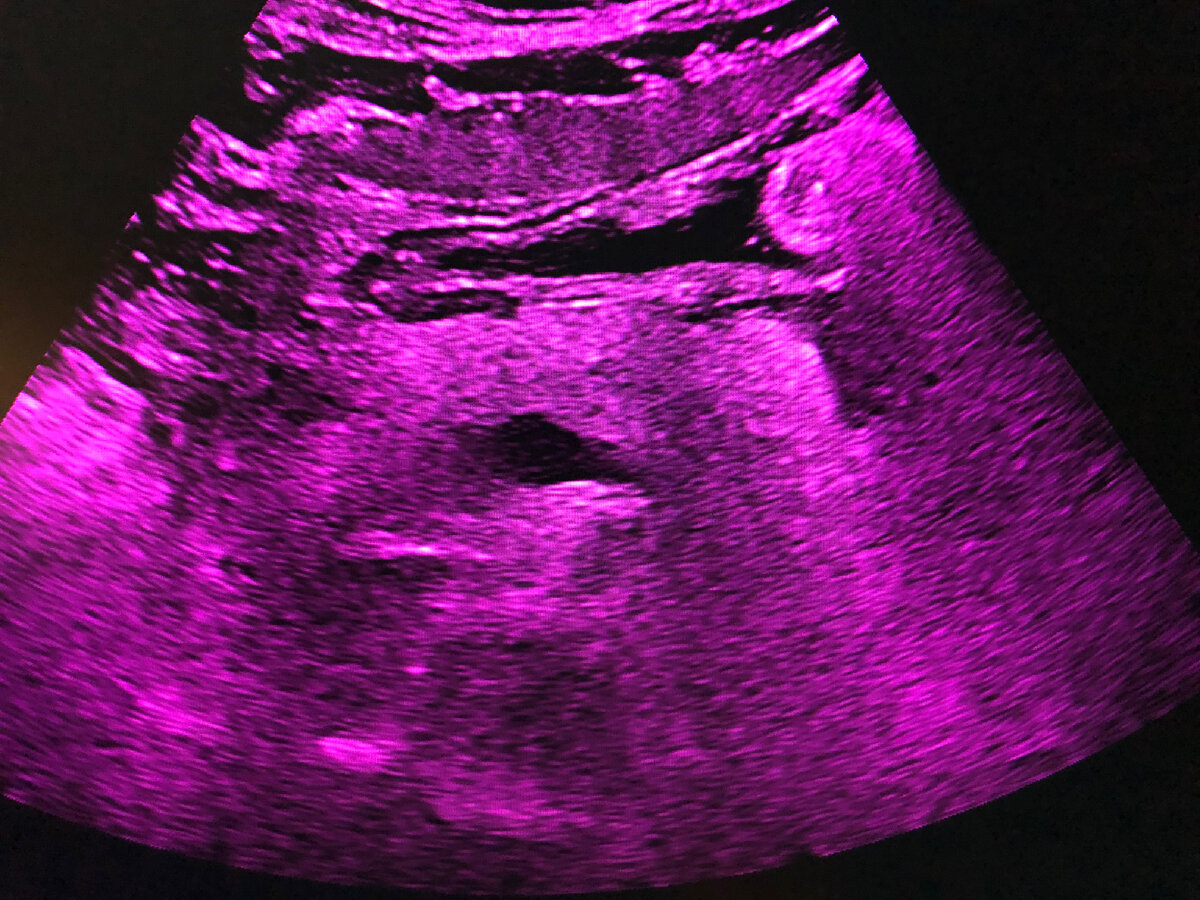

Липоматоз поджелудочной железы

✳️Липоматоз (стеатоз, жировая инфильтрация, неалкогольная жировая болезнь) поджелудочной железы (ЛПЖ) - это жировая дистрофия органа, выполняющего пищеварительную и эндокринную функции.